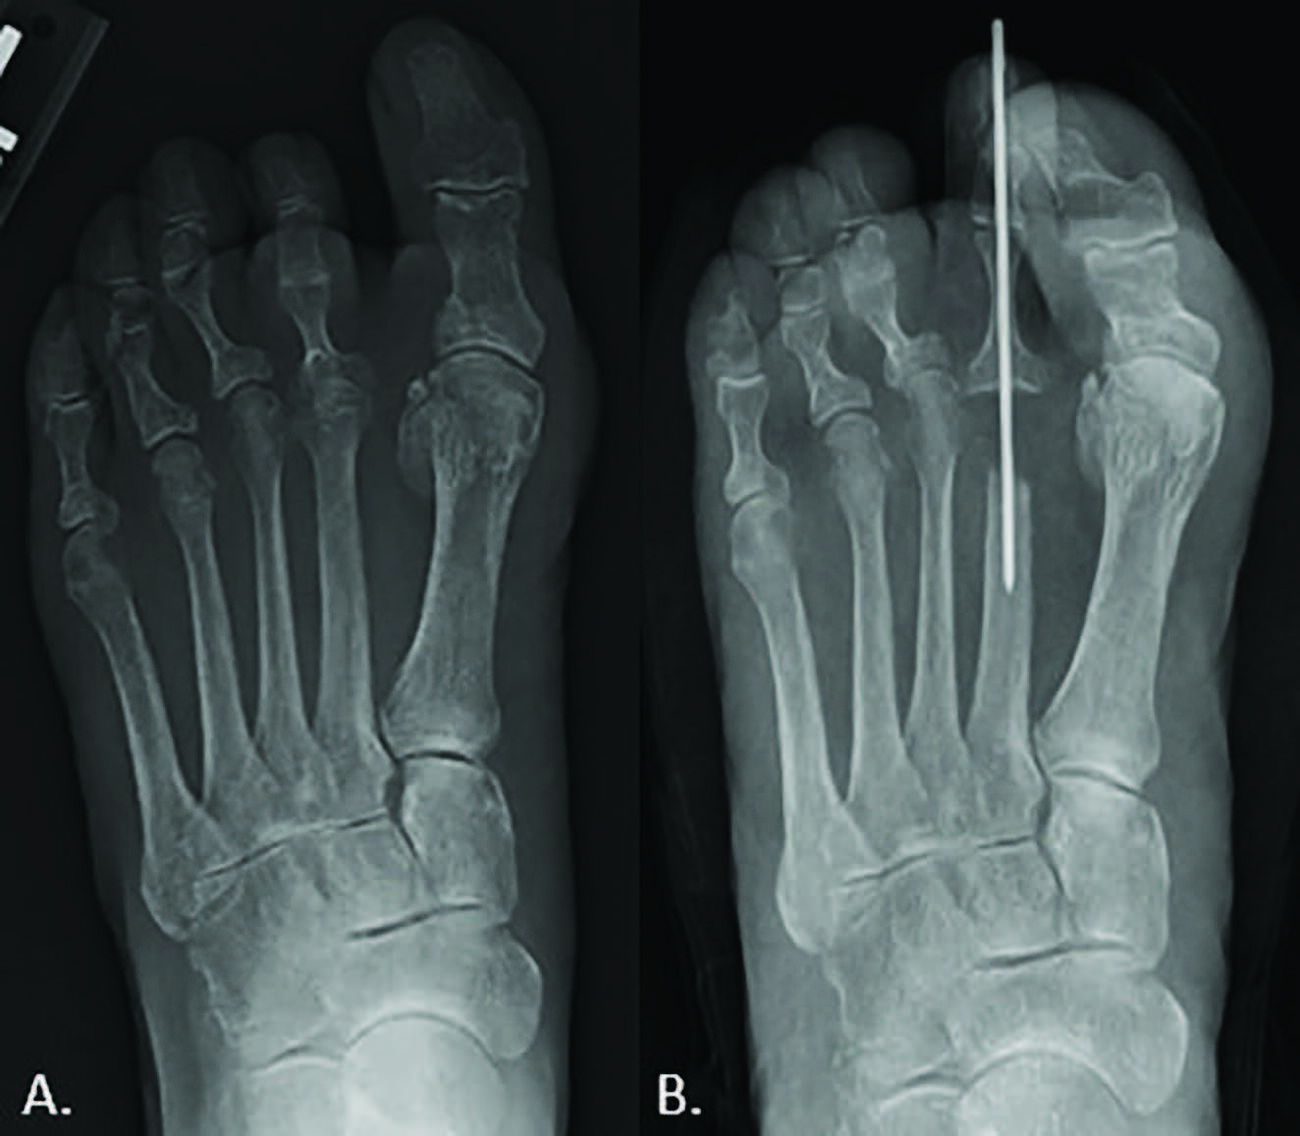

Degenerative joint disease (DJD) can be debilitating and result in functional deficits and low quality of life for the patient. DJD in the metatarsophalangeal joints (MPJ) of the foot has various treatment options, depending on the joint affected. Unfortunately, there are limited treatment options when specifically looking at DJD involving the less common second MPJ (see first photo above). Procedures to address arthritic pain at the second MPJ typically fall into two categories, either joint sparing or joint destructive. Treatment options vary depending on the preoperative pathology as well as patient-specific characteristics.

Weight-bearing radiographs allow for evaluation of biomechanical relationships of the foot, including the metatarsal parabola and concomitant hallux abductovalgus deformity. In our practice, we find that weight-bearing radiographs of the whole foot are more advantageous than isolated digital radiographs, as it allows us to better understand foot structure, deformities, and adjacent pathology. One can visualize joint space narrowing and periarticular osteophytes on radiographs in addition to congenital abnormalities involving the second metatarsal or surrounding structures. Advancing imaging including magnetic resonance imaging (MRI), arthrogram, and MR arthrogram may be required when concern for avascular necrosis is present. The authors find that an arthrogram is extremely useful to evaluate capsular integrity.